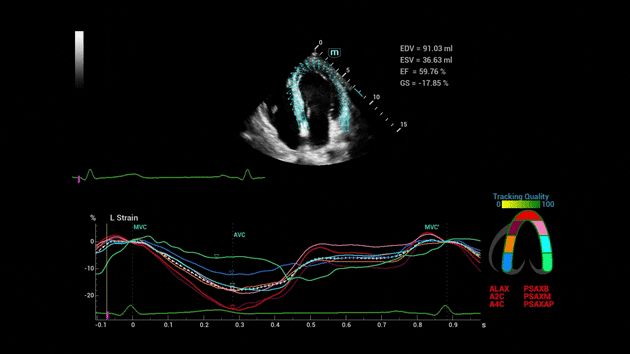

Consona presenta soluzioni nuove e concrete, che aiutano a effettuare diagnosi efficaci con semplicitĂ , rivolgendosi a un'ampia platea di pazienti. La serie mette a disposizione strumenti estremamente avanzati per rimanere all'avanguardia nella diagnosi cardiovascolare.